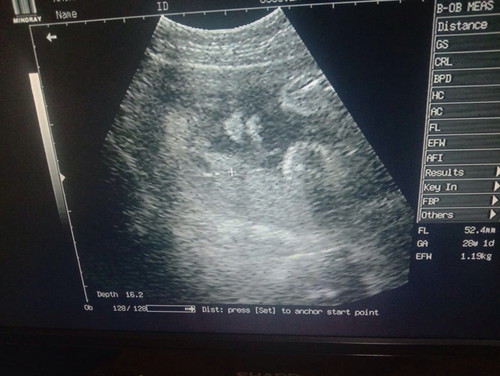

ตอน28w ลูกในท้องของแม่น้ำหนักเท่าไหร่กันบ้างค่ะ บ้านนี้น้องหนัก 1,119 คะ